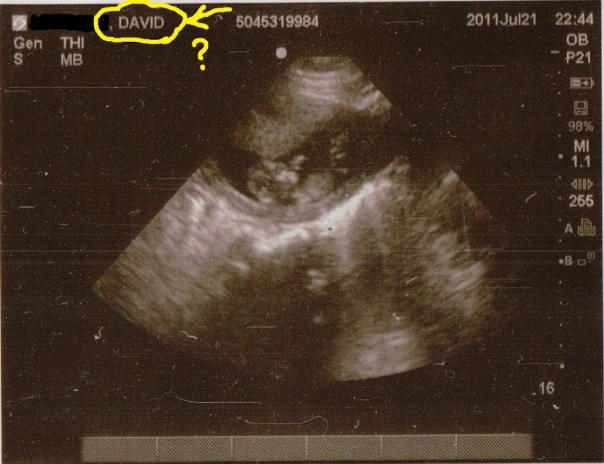

The doctor did an abdominal ultrasound (thank goodness), he showed us the baby and it appeared to have a good, strong heartbeat. He didn’t do the thing where they measure the heartbeat and tell you the number. Either this machine didn’t do that or he didn’t know how. So while we didn’t get a number of how strong the heartbeat was, we could see it and it looked good. The baby wasn’t moving (probably sleeping), although I thought I saw an arm move just a little.

The doctor said he was waiting on my test results and then we could go home. I was to call my ob the next day to let them know what was going on and to come back to the ER if I started soaking pads (I was barely bleeding at this point). Then he gave us a copy of the ultrasound. My husband looked at it and said to me, “Is your name, David?”

There on my ultrasound was the name David So-and-so, who I assume is the guy that got his ultrasound before me and the doc never bothered to change the name. Boy, won’t David be surprised to find out he has a uterus…and he’s pregnant!